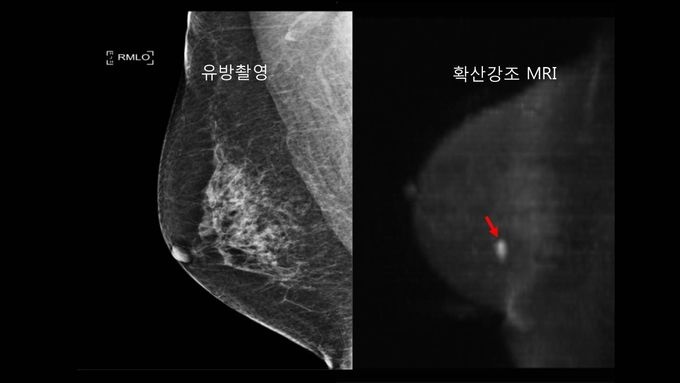

µ¥Àϸ®¸Þµð ¹Ú´ëÁø ±âÀÚ] Ãʱâ À¯¹æ¾Ï ¹ß°ß¿¡ Á¶¿µÁ¦¸¦ ÁÖ»çÇÒ Çʿ䰡 ¾ø°í °Ë»ç ½Ã°£ÀÌ ÂªÀº È®»ê°­Á¶ MRI°¡ À¯¹æÃÔ¿µ°ú ÃÊÀ½ÆÄº¸´Ù ¿ì¼öÇÏ´Ù´Â ¿¬±¸°á°ú°¡ ¹ßÇ¥µÆ´Ù.

¼­¿ï´ëº´¿ø À¯¹æ¼¾ÅÍ´Â À¯¹æ¾Ï Ç¥Áذ˻çÀÎ ÃÔ¿µ°ú ÃÊÀ½ÆÄ¸¦ º´ÇàÇßÀ» ¶§º¸´Ù È®»ê°­Á¶ MRIÀÇ ¾Ï ¹ß°ßÀ²ÀÌ 2¹è ³ô¾Ò´Ù°í 22ÀÏ ¹àÇû´Ù.

À¯¹æ¾Ï ¹ß°ßÀ²Àº ¡âÀ¯¹æÃÔ¿µ 9¸í(1000¸í ´ç 8¸í) ¡âÀ¯¹æÃÔ¿µ+À¯¹æÃÊÀ½ÆÄ 12¸í(1000¸í ´ç 10¸í) ¡âÈ®»ê°­Á¶ MRI 25¸í(1000¸í ´ç 22¸í)À¸·Î È®»ê°­Á¶ MRI°¡ ¿ùµîÇÏ°Ô ³ô¾Ò´Ù.

¹ß°ßµÈ ¾ÏÀº ¸ðµÎ ¾×¿Í ¸²ÇÁÀýÀüÀ̰¡ ¾ø´Â Ãʱ⠾ÏÀ̾úÀ¸¸ç Æò±Õ Å©±â´Â 1cm¿´´Ù. Á¶Á÷°Ë»çÀÇ ¾ç¼º ¿¹Ãøµµ ¿ª½Ã È®»ê°­Á¶ MRI´Â 42%, ÃÔ¿µ°ú ÃÊÀ½ÆÄ´Â 19%·Î À¯ÀÇÇÏ°Ô ³·¾Ò´Ù.

Á¶¿µÁõ°­ MRI °Ë»ç·Î À¯¹æ¾ÏÀ» Á¤È®È÷ Áø´ÜÇÒ ¼ö ÀÖ´Ù°í ¾Ë·ÁÁ® ÀÖÁö¸¸ Á¶¿µÁ¦ ºÎÀÛ¿ë À§Ç輺°ú °íºñ¿ë ¹®Á¦·Î Á¢±Ù¼ºÀÌ ¶³¾îÁ® °íÀ§Ç豺 Á¶Â÷ MRI ÀÌ¿ëÀÌ ¹Ì¹ÌÇÑ ½ÇÁ¤ÀÌ´Ù.

±âÁ¸ Á¶¿µÁõ°­ MRI¿¡ º¸Á¶ÀûÀ¸·Î¸¸ »ç¿ëµÆ´ø È®»ê°­Á¶ MRI°¡ ÃÖ±Ù ±â¼úÀû ¹ßÀüÀ» °ÅµìÇØ ºü¸¥ ½Ã°£ ³»¿¡ °íÇØ»ó À¯¹æ¿µ»óÈ­°¡ °¡´ÉÇØÁ® Ãʱâ¾Ï ¹ß°ß¿¡ »õ·Î¿î ´ë¾ÈÀ¸·Î ¶°¿À¸£°í ÀÖ´Ù.

È®»ê°­Á¶ MRI´Â Á¶Á÷ ³»¿¡¼­ ¹° ºÐÀÚ ¿òÁ÷ÀÓÀ» ÃøÁ¤ÇØ ¿µ»óÈ­ÇÏ´Â ±â¼ú·Î ¾Ï Á¶Á÷Àº ÁÖÀ§ Á¤»óÁ¶Á÷°ú ºñ±³ÇØ ¹° ºÐÀÚ È®»êµµ°¡ ÁÙ¾îµé¾î °í½ÅÈ£·Î º¸ÀÌ°Ô µÈ´Ù.

°Ë»ç½Ã°£ÀÌ 5ºÐ Á¤µµ·Î ª°í Á¶¿µÁ¦¸¦ ÁÖ»çÇÏÁö ¾Ê¾Æ ÀÓ»êºÎ, Á¶¿µÁ¦ ¾Ë·¹¸£±â°¡ Àְųª ½ÅÀå±â´ÉÀÌ ÀúÇϵŠÀÖ´Â ¿©¼º¿¡¼­µµ ¾ÈÀüÇÏ°Ô »ç¿ë °¡´ÉÇÏ´Ù.